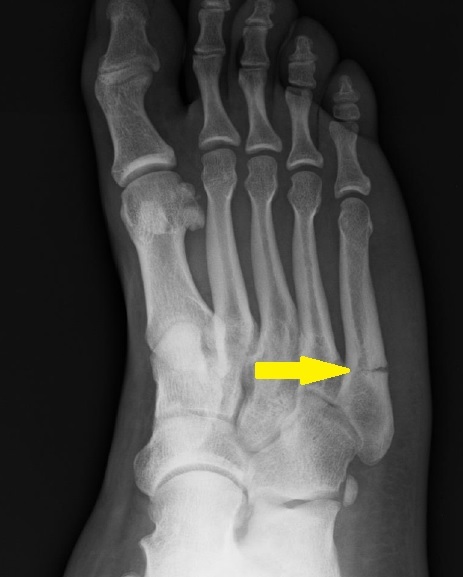

Identify

Jones fracture

(fracture of the base of the 5th metatarsal)